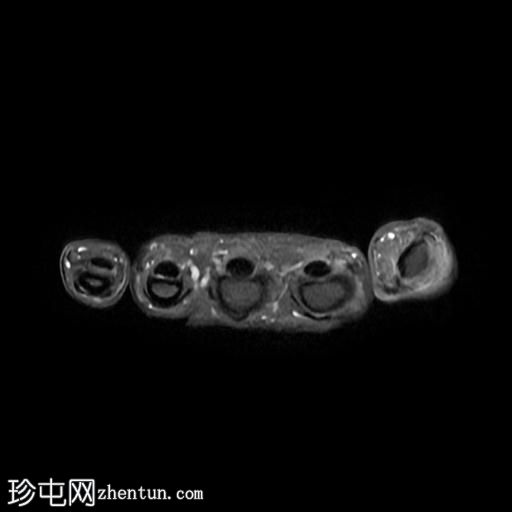

轴位PD脂肪抑制像

7.jpg